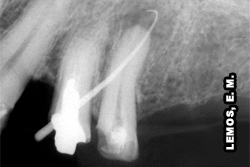

Periodontite Apical Aguda - microbiana

fonte: www.endo-e.com

Periodontite apical aguda - traumática

A Periodontite apical aguda, pode ou não estar associada a uma área radiolúcida periapical.

O “espessamento” do espaço correspondente ao ligamento periodontal pode ser um achado radiográfico da Periodontite Apical Aguda.

Entretanto, normalmente esse espaço apresenta-se normal e a lâmina dura, intacta.